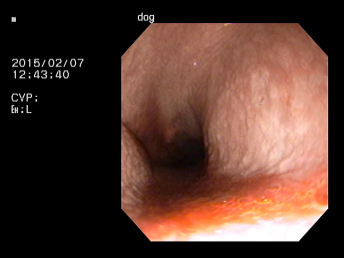

慢性的にくしゃみ、鼻水がでているわんちゃんの鼻腔内観察および生検を行いました。

口から内視鏡をいれ、咽頭部、鼻腔内と進めていきます。

病変部です。血液の混じった粘性のある鼻汁。粘膜には炎症所見が確認できます。

この子は生検により鼻から出血しないよう、滅菌ブラシにて生検を行ないました。